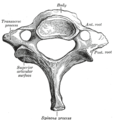

• الفقرة العنقية الثانية أو المحور Axis: لها نتوء مميز وهو ينشأ من جسم هذه الفقرة ومنها يرتفع إلى أعلى بشكل عمودي ليمر عبر حلقة الفهقة ويشده في مكانه رابط يسمى الرابط المستعرض. وتدور وتستقر فقرة الفهقة على فقرة المحور.

والشوكة كبيرة وتتصل بها العضلات.